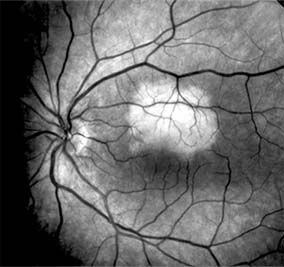

Nonexudative age-related macular degeneration is characterized by variable degrees of atrophy and degeneration of the outer retina, retinal pigment epithelium, Bruch's membrane and choriocapillaris. Of the ophthalmoscopically visible changes in the retinal pigment epithelium and Bruch's membrane, drusen are the most typical (Figure 10-1). Drusen are discrete, round, yellow-white deposits of variable size beneath the pigment epithelium and are scattered throughout the macula and posterior pole. With time, they may enlarge, coalesce, calcify, and increase in number. Histopathologically, most drusen consist of focal collections of eosinophilic material lying between the pigment epithelium and Bruch's membrane; they therefore represent focal detachment of the pigment epithelium. In addition to drusen, clumps of pigment irregularly dispersed within depigmented areas of atrophy may progressively appear throughout the macula. The level of associated visual impairment is variable and may be minimal. Fluorescein angiography demonstrates irregular patterns of retinal pigment epithelial hyperplasia and atrophy. Electrophysiologic testing in most patients is normal.

Figure 10-1

Figure 10-1: Age-related macular degeneration with discrete (small arrow) and large confluent (large arrow) macular drusen.